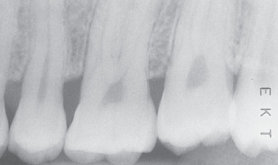

Elongation

What it looks like:

Teeth appear long and stretched.

Cause:

Insufficient vertical angulation.

Fix:

Increase vertical angulation.